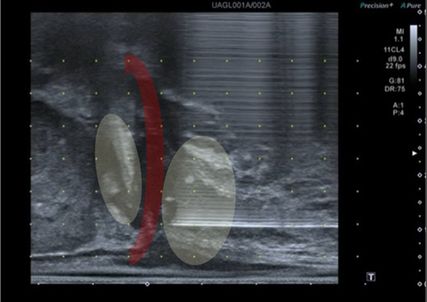

Abb. 2: Sonografische Darstellung der tiefen Beckenbodenmuskulatur (rot) und der Prostataapex. In Gelb dargestellt sind die Applikationsorte der tiefen Lokalanästhesie vor perinealer Prostatabiopsie